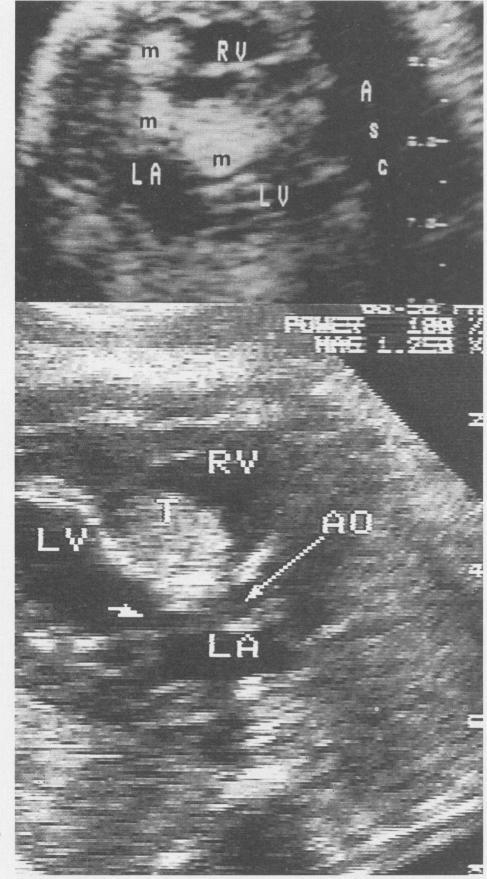

心脏超声检查在结构性异常和心律失常中的应用。识别与治疗。

Cardiac ultrasonography in structural abnormalities and arrhythmias. Recognition and treatment.

Fetal cardiac ultrasonography has become an important tool in the evaluation of fetuses at risk for cardiac anomalies. It can both guide prenatal treatment and assist the management and timing of delivery. We recommend that a fetal echocardiogram be done when there is a family history of congenital heart disease; maternal disease that may affect the fetus; a history of maternal drug use, either therapeutic or illegal; evidence of other fetal abnormalities; or evidence of fetal hydrops. The optimal timing of evaluation is 18 to 22 weeks' gestation. An entire range of structural cardiac defects can be visualized prenatally, including atrioventricular septal defect, ventricular septal defect, cardiomyopathy, ventricular outlet obstruction, and complex cardiac defects. The outcome for a fetus with a recognized abnormality is unfavourable, with less than 50% surviving the neonatal period. Fetal cardiac arrhythmias are also a common occurrence, 15% in the series described here. Premature atrial or ventricular contractions are most commonly seen and usually require no treatment. Supraventricular tachycardia can result in hydrops and require in utero treatment to prevent fetal demise. Complete heart block, particularly in association with structural heart disease, has a poor prognosis for fetal survival.

胎儿心脏超声检查已成为评估有心脏异常风险胎儿的重要工具。它既可以指导产前治疗,又有助于分娩的管理和时机选择。我们建议,当存在先天性心脏病家族史、可能影响胎儿的母体疾病、母体有治疗性或非法药物使用史、其他胎儿异常证据或胎儿水肿证据时,应进行胎儿超声心动图检查。最佳评估时机是妊娠18至22周。产前可以看到一系列结构性心脏缺陷,包括房室间隔缺损、室间隔缺损、心肌病、心室流出道梗阻和复杂心脏缺陷。已确诊异常的胎儿预后不佳,新生儿期存活率不到50%。胎儿心律失常也很常见,在此系列研究中占15%。最常见的是房性或室性早搏,通常无需治疗。室上性心动过速可导致水肿,需要宫内治疗以防止胎儿死亡。完全性心脏传导阻滞,尤其是与结构性心脏病相关时,胎儿存活预后不良。